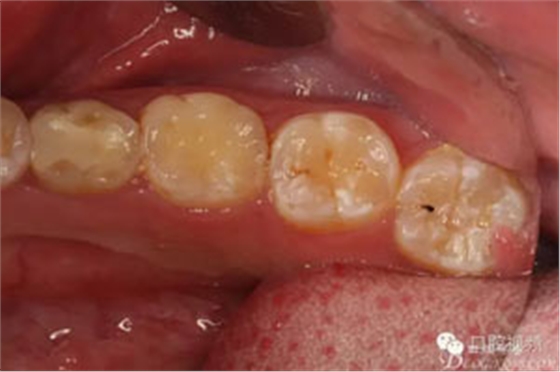

圖3.術(shù)前口內(nèi)照片,舌側(cè)外形無隆起。光滑平整。